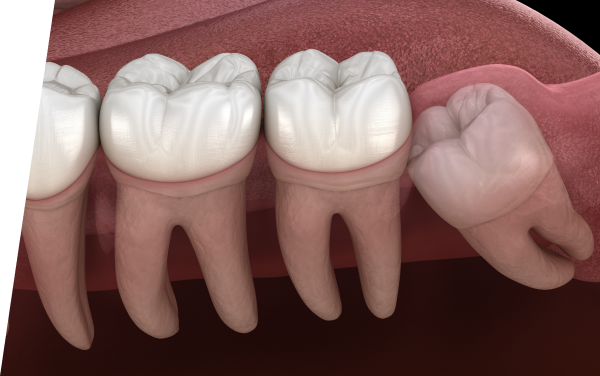

- 斜めや横向きに生えている

- 完全に親知らずが埋まっている

2回目の診察親知らずの抜歯

親知らずの抜歯は局所麻酔で痛みを抑え、安全に行います。歯の生え方に応じて切開や縫合が必要な場合もありますが、術中も不安なく受けられるよう配慮して進めます。